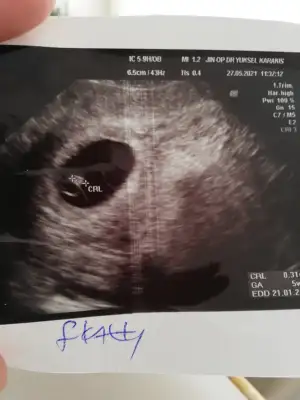

Eklentiler

• 16229775023891250001376631358539.webp

16229775023891250001376631358539.webp

27,1 KB · Görüntüleme: 51